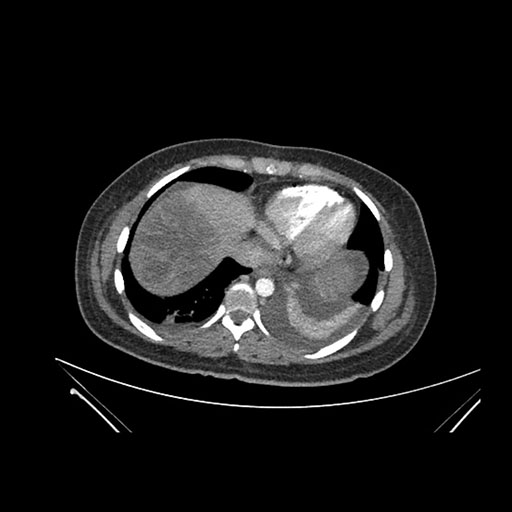

Imaging Analysis

Look through the patient's CT scan to identify any areas of concern for the necessary procedure.

Axial Venous

Based on initial findings, which issue(s) would you be most concerned about?